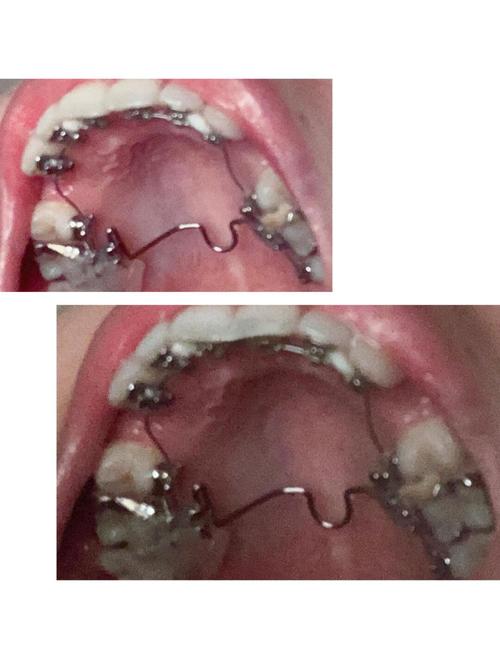

根据方案选择矫治器(如传统金属托槽、陶瓷托槽、隐形矫治器等),医生会将托槽粘接在牙齿表面(或佩戴隐形牙套),通过弓丝、橡皮筋等施加持续、轻柔的力,使牙齿在牙槽骨中缓慢移动至理想位置,治疗周期通常为1.5-3年,期间每4-6周复诊一次,调整矫治力、更换弓丝或牙套。